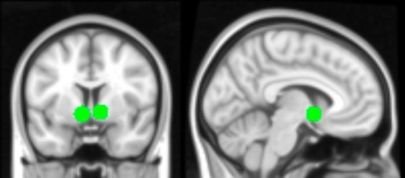

بررسی تاثیر رسانه‌های اجتماعی روی مغز نوجوانان

ICTPRESS - پژوهش جدید محققان دانشگاه کالیفرنیا در لس‌آنجلس حاکی از آن است که مدارهای مغزی مرتبط با شرط بندی و شکلات در مغز نوجوانان در زمان استفاده از رسانه‌های اجتماعی فعال میشوند.